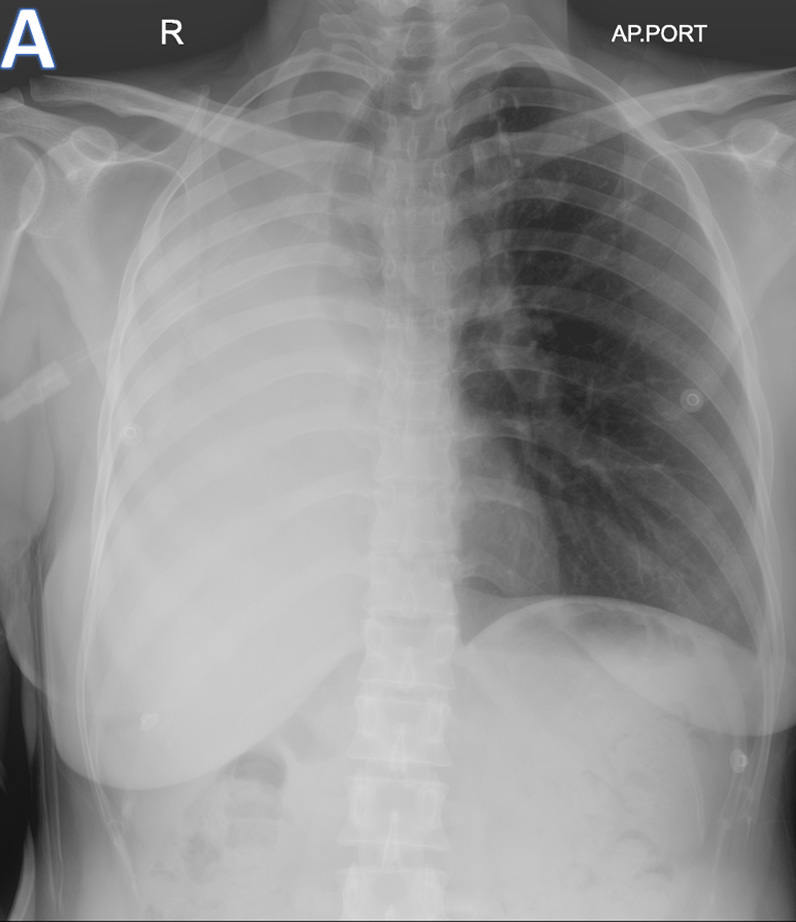

A - AP-Chest XRAY

• ARROW: Tracheal deviation to the Right.

• STAR: Opacified right hemithorax.

• Findings are consistent with Collapse of the right lung.